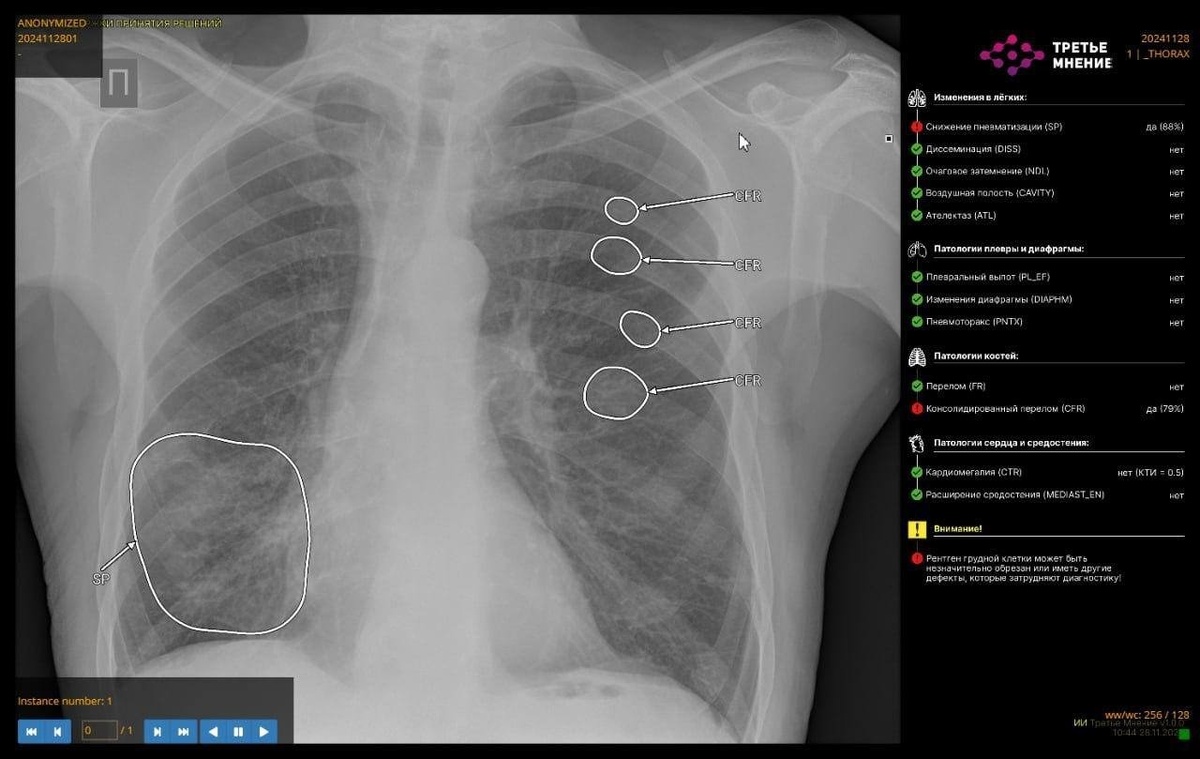

Он отметил, что лучевые диагносты 50 больниц используют искусственный интеллект для интерпретации исследований и получения второго мнения. Например, на КТ органов грудной клетки ИИ-сервис способен определять до 14 видов патологий.

Министр назвал направления, которые выявляют с помощью нейросетей. Это пневмоторакс, изменения подмышечных лимфоузлов на КТ органов грудной клетки, переломы ребер, инфильтрация легочной ткани (пневмония), плеврит (скопление жидкости в плевральной полости), объемное образование надпочечников, костная патология позвоночника.

«ИИ-сервисы уже компетентны в анализе изменения лимфоузлов: сервис подсвечивает врачам патологическую зону, которую в дальнейшем врач клиницист сопоставляет с результатами исследования и симптомами», — отметил министр.